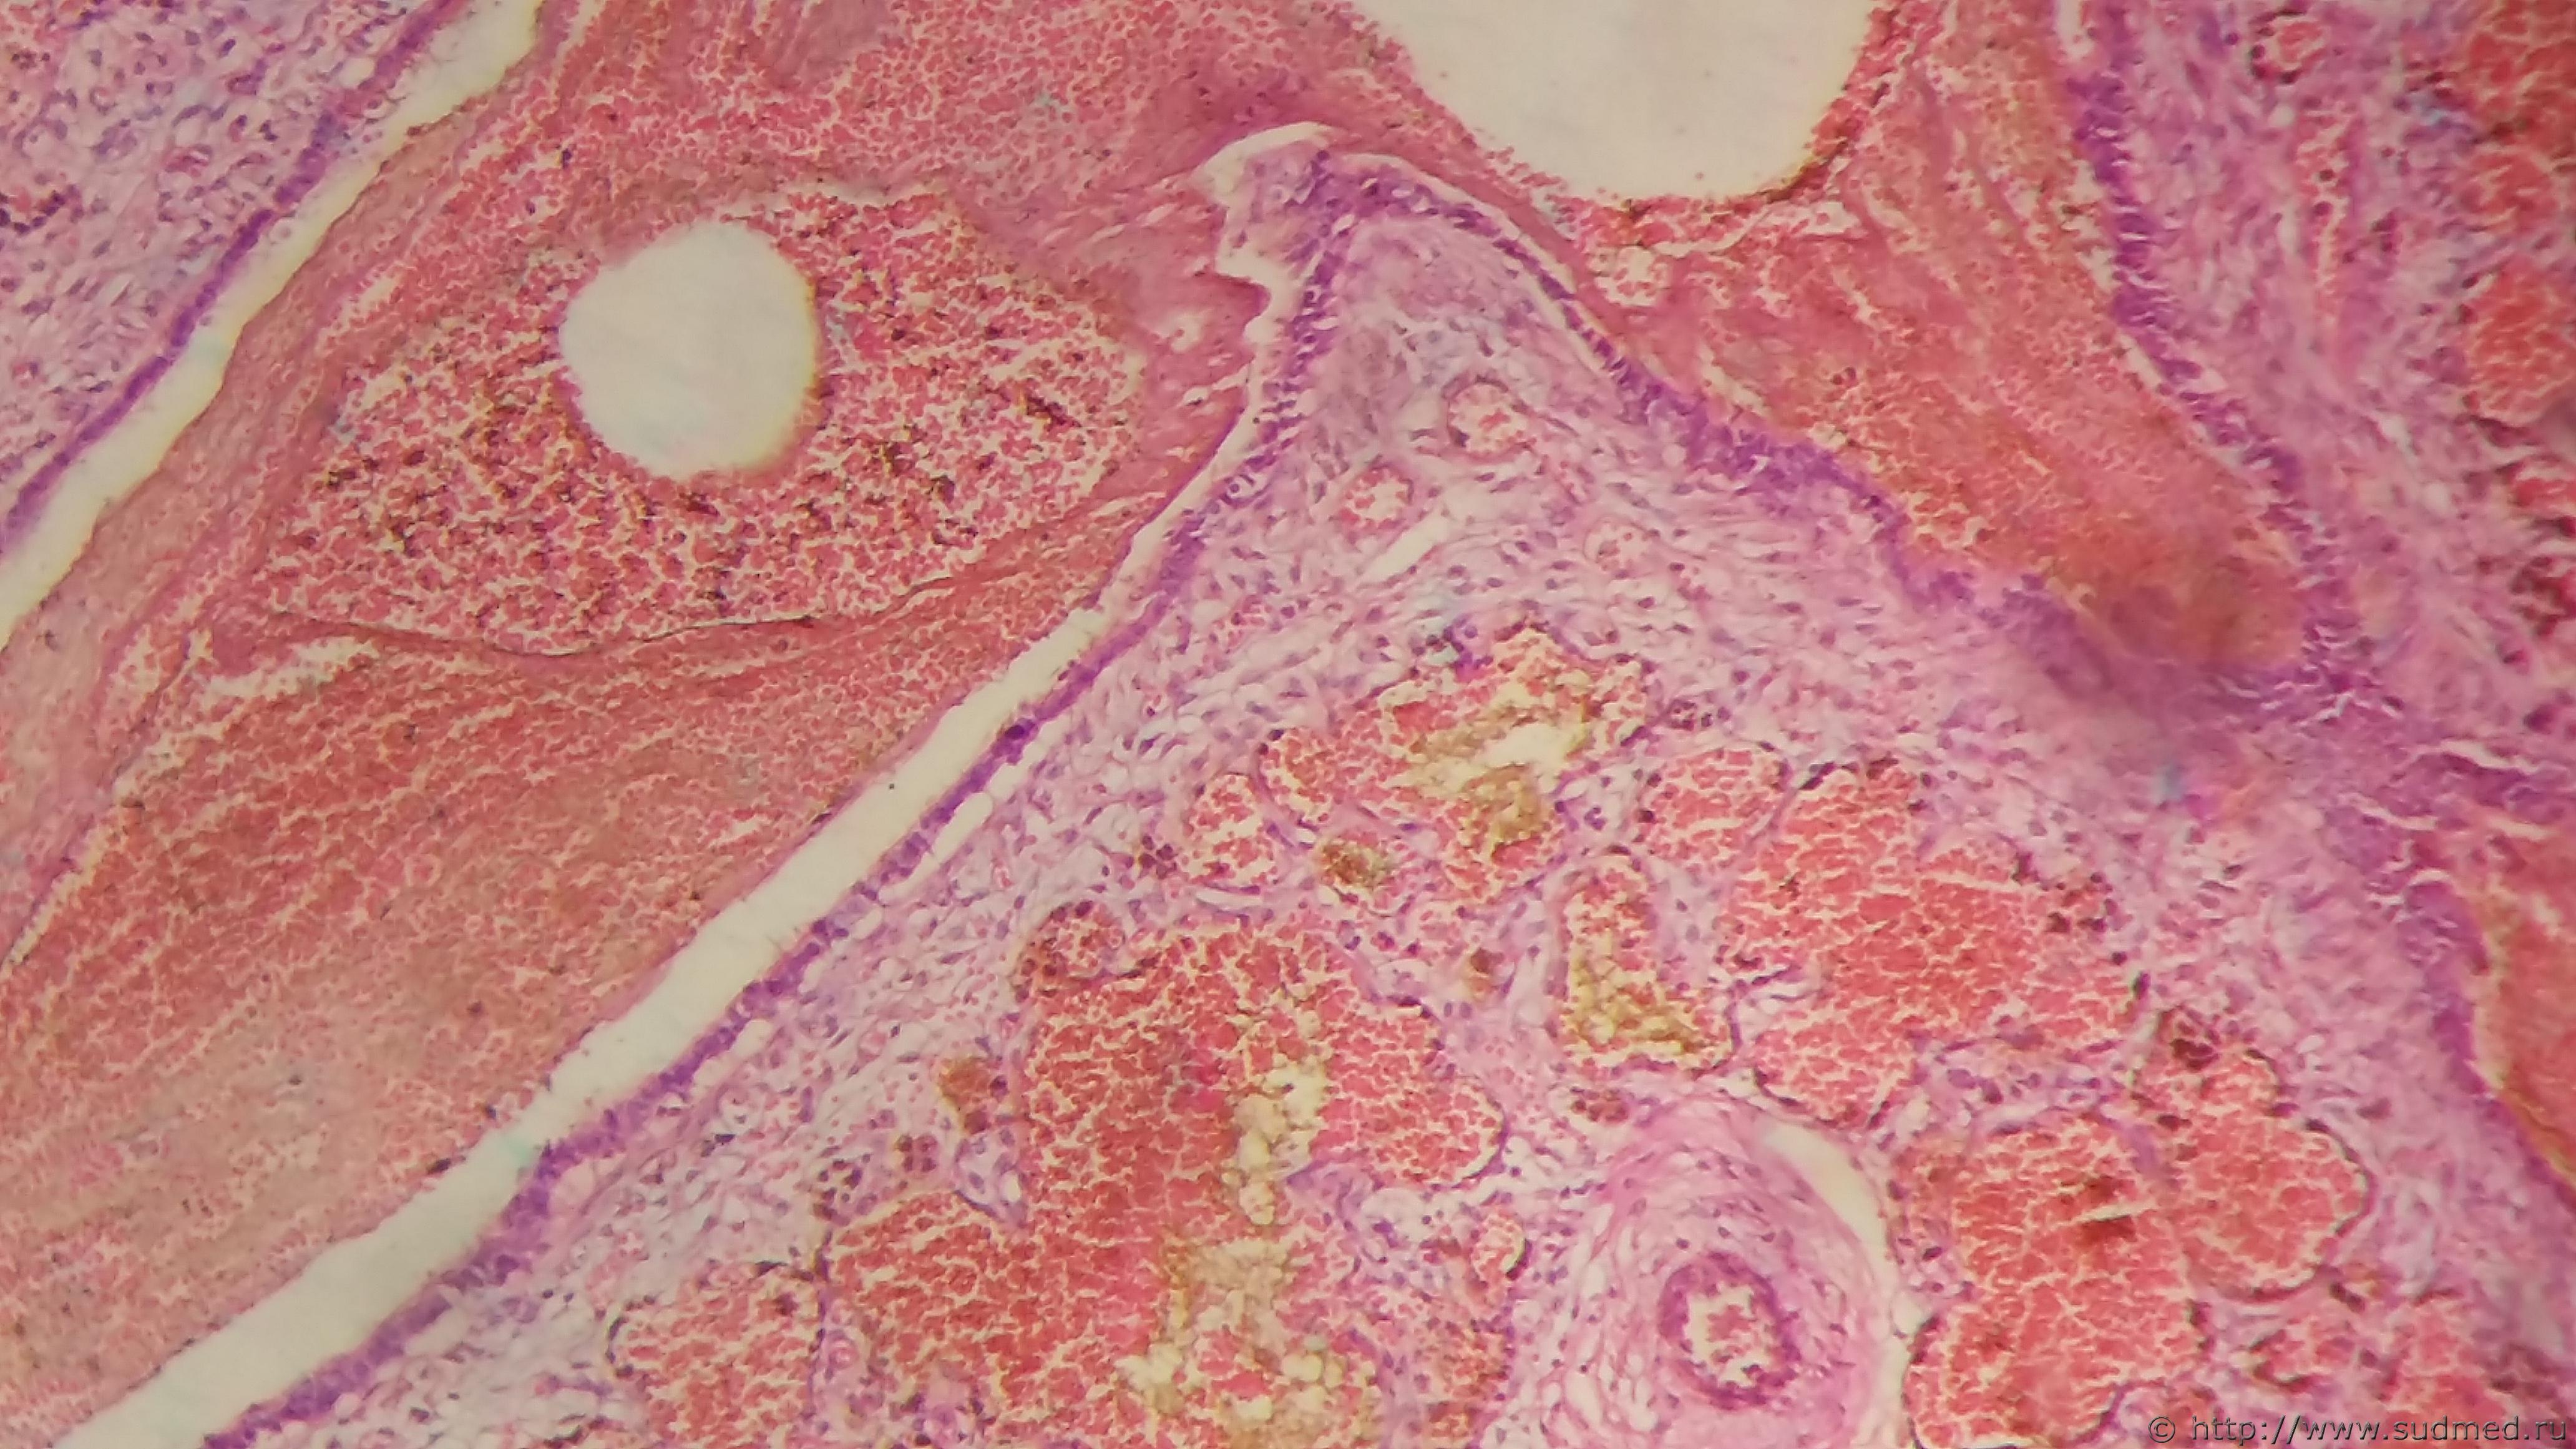

Женщина 30 лет. Карциноид-туморлет в легких